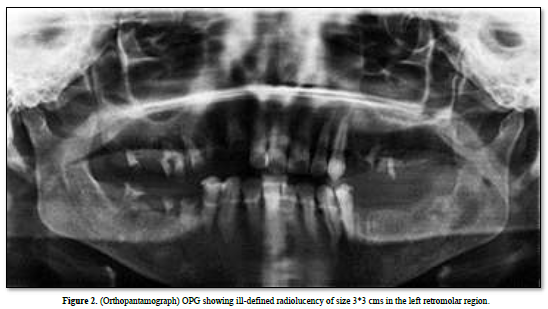

Complete blood investigations revealed an elevated lymphocytic count and elevated ESR. OPG examination showed an ill-defined radiolucency in the retromolar region of 3x3 cm in size, involving the inferior alveolar canal (Figure 2).